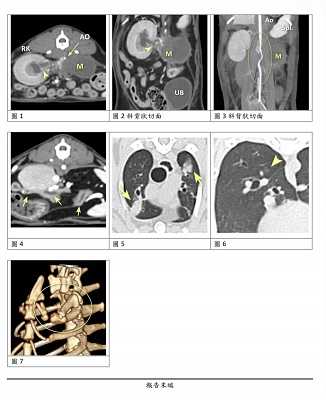

後安排2026年1月1日於長青醫院進行CT斷層掃描,此次在麻醉前血壓偏高,少量麻醉藥便進行插管。但在麻醉過程中出現明顯低心率以及低血壓的情形,施打一針強心針後於10分鐘內完成掃描。

麻醉氣體關閉後血壓迅速回升,可能與腎臟疾病/腎腫瘤造成的高血壓相關。且在麻醉恢復過程明顯心律不整。術後恢復也花了較長時間醒來。初步判斷,左腎有明顯腫大,右腎看起來沒有正常血流通過,結構不正常。總體來說大白的狀況明顯非常不好。

大白沐恩檢查中發現左腎有團塊,這次來長青做電腦斷層掃描。

麻醉前血壓偏高,少量麻醉藥便可以進行插管。麻醉過程出現明顯低心率以及低血壓的情形,施打一針強心針後於10分鐘內完成掃描。

麻醉氣體關閉後血壓迅速回升,可能與腎臟疾病/腎腫瘤造成的高血壓相關。

*麻醉恢復過程明顯心律不整。術後恢復也花了較長時間醒來。若需再次接受麻醉,建議穩定高血壓,做術前心肺評估,並減少麻醉用藥的劑量。初步判斷,左腎有明顯腫大,右腎看起來沒有正常血流通過,結構不正常。